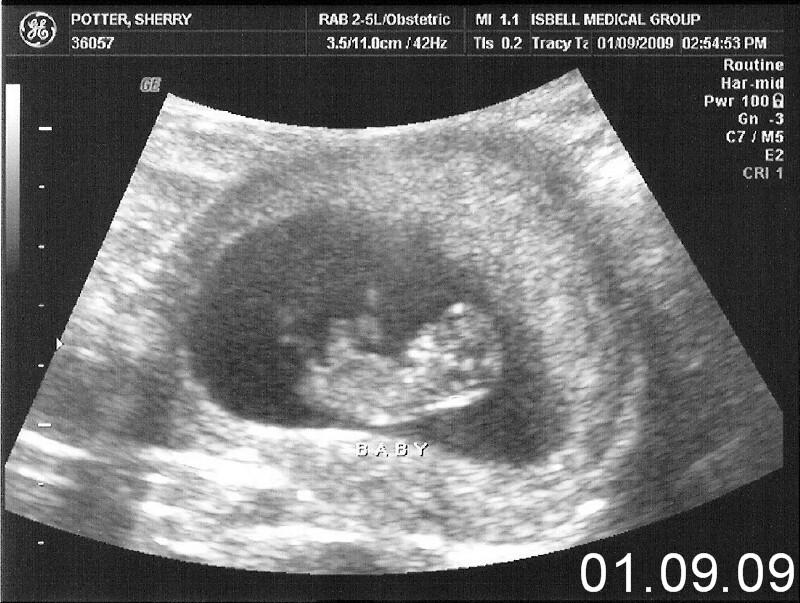

Hayley Grace January 09, 2009